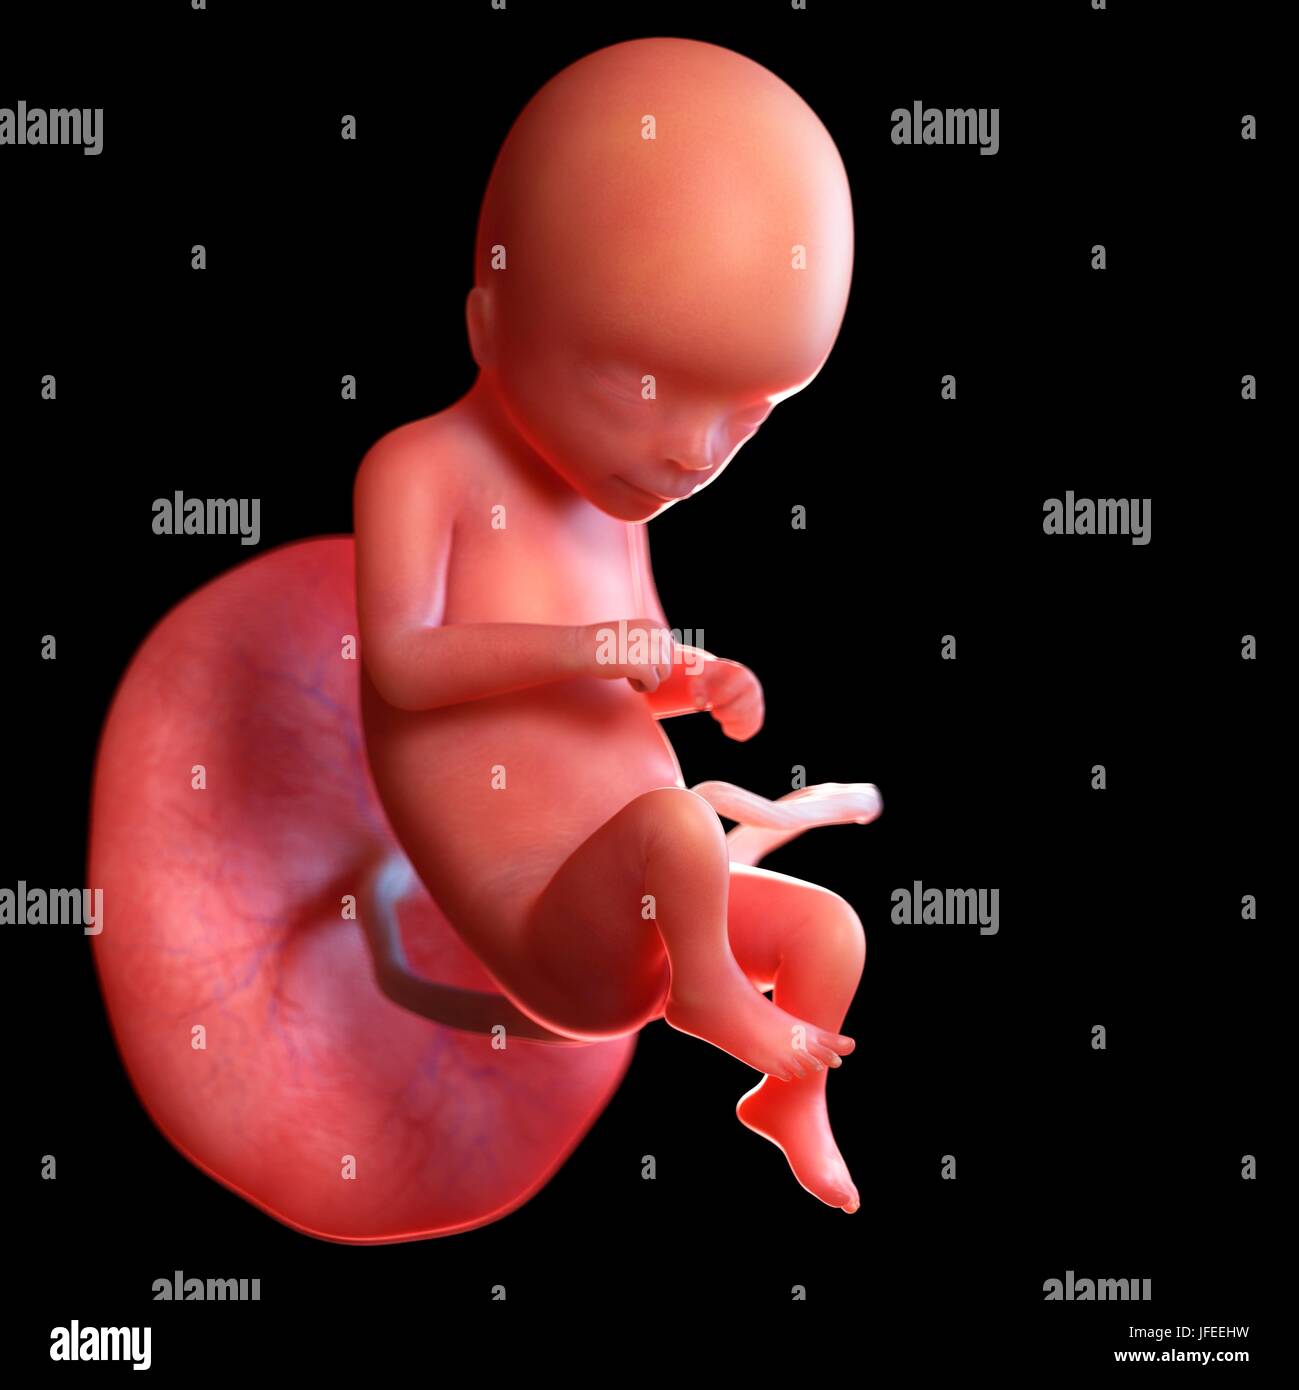

L Evoluzione Del Feto Il Tuo Bimbo

Lo Sviluppo Fetale Paola Zamperinipaola Zamperini

Lo Sviluppo Del Feto In Gravidanza Blogmamma It

Lo Sviluppo Dell Embrione Feto

Lo Sviluppo Del Feto Tra La 9 E La 16 Settimana Nostrofiglio It

Sviluppo Del Feto